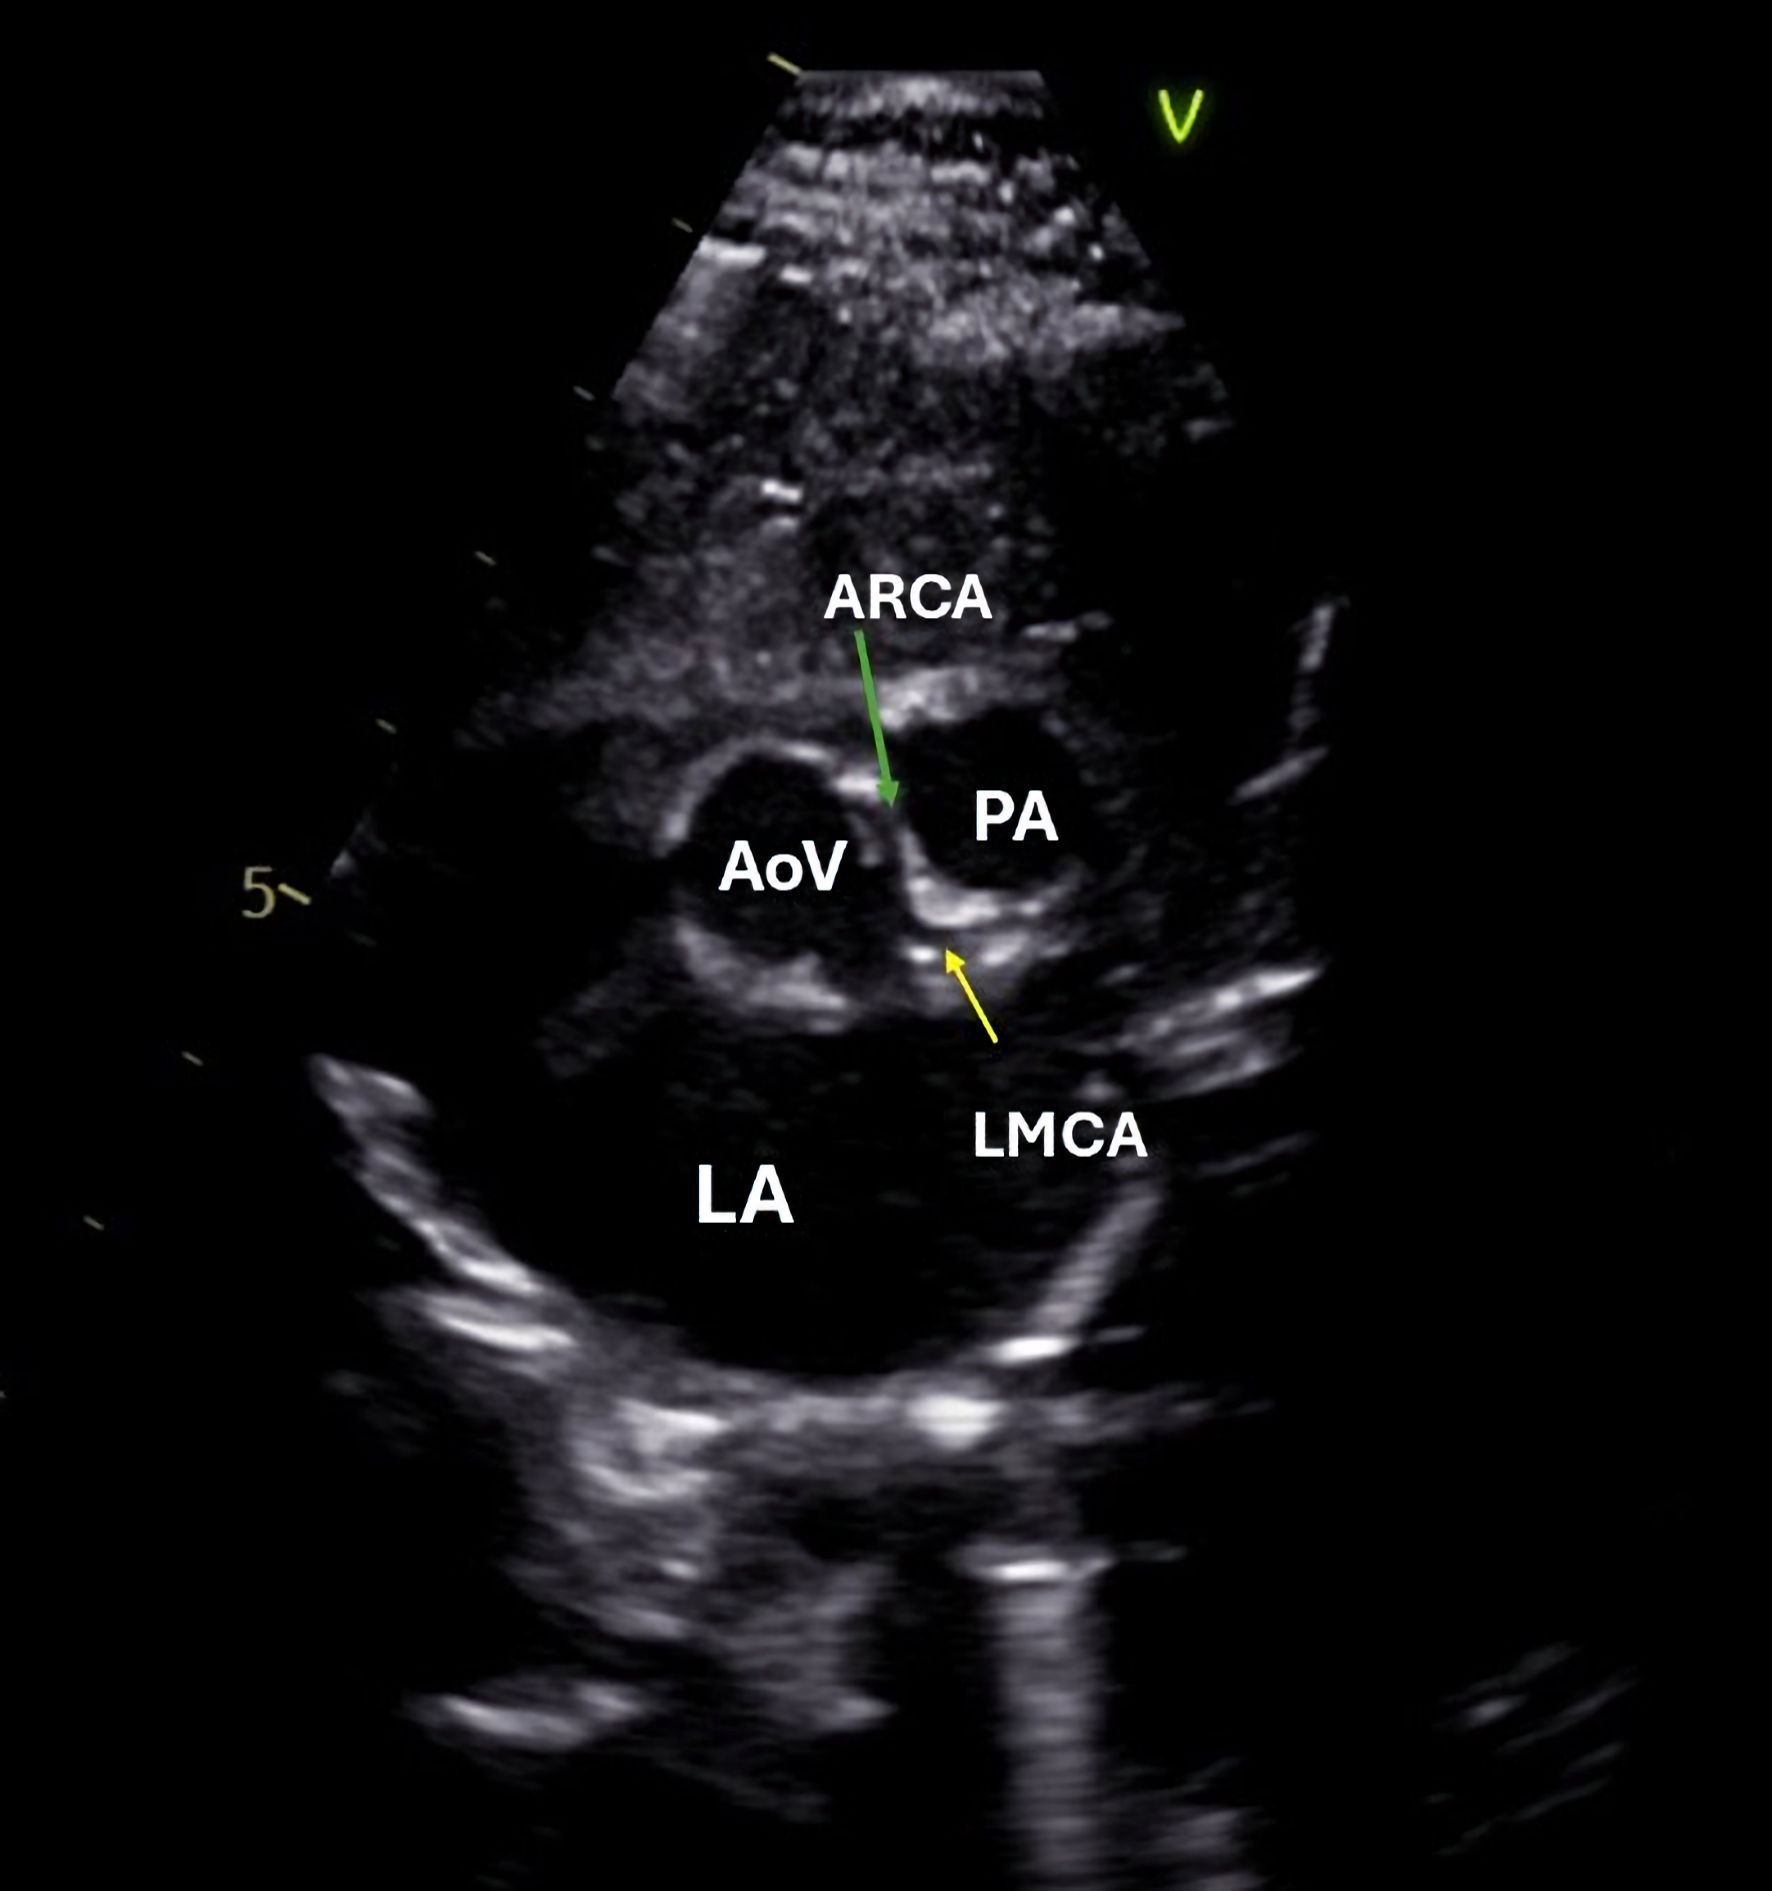

Laboratory investigations are shown in Table 1. Chest radiograph showed a normal cardiothymic silhouette and mild hyperinflated lung fields. Electrocardiogram traced normal sinus rhythm and rate, and without abnormalities in ST- and T-waves. The mean SpO2 (%) and standard deviation (SD) by continuous pulse oximetry on the foot was 98.7 (SD = 1.5). Anomalous origin of the right coronary artery with interarterial course and a small patent foramen ovale were identified on transthoracic echocardiogram (Fig. 1).

Figure 1. Two-dimensional echocardiography demonstrated right coronary artery arising from the left coronary cusp on cross-sectional parasternal short axis view. The yellow and green arrows indicate the LMCA and ARCA, respectively. AoV: aortic valve; ARCA: anomalous right coronary artery; LMCA: left main coronary artery; PA: pulmonary artery; LA: left atrium.

On hospital admission, the pediatric cardiologist was consulted to address the combination of cyanosis and a nonspecific heart murmur on auscultation. The fetal echocardiogram was negative for congenital heart defects. The chest radiograph and 12-lead electrocardiogram were not diagnostic. Anomalous origin of the right coronary artery from the left coronary cusp with interarterial course was detected on two-dimensional transthoracic echocardiogram.